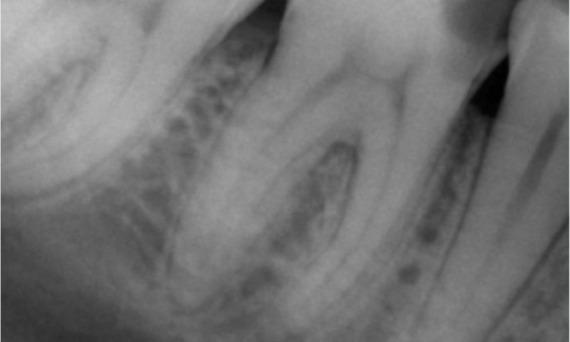

"Ich habe mich für TruNatomy entschieden, um so viel Dentin wie möglich zu erhalten, um die okklusale Belastung zu bewältigen und die Langlebigkeit des Zahns zu erhöhen." Dr. Abuelezz

Vorher: Bei der Untersuchung wurde eine Karies-Läsion am unteren rechten ersten Molaren festgestellt. Bei der röntgenologischen Untersuchung zeigte sich die Nähe der Läsion zum Pulpahorn. Zusammen mit den Hauptbeschwerden wurde die endgültige Diagnose einer chronischen irreversiblen Pulpitis gestellt.

Nachher: Die Zugangskavität wurde so konservativ wie möglich gestaltet. Da es sich um einen jungen Patienten handelte, war TruNatomy das System der Wahl. Wir mussten das Dentin so weit wie möglich erhalten, um die Fähigkeit des Zahns zur Bewältigung der okklusalen Belastung und die Langlebigkeit der endgültigen Restauration zu erhöhen.

Kairo, Ägypten